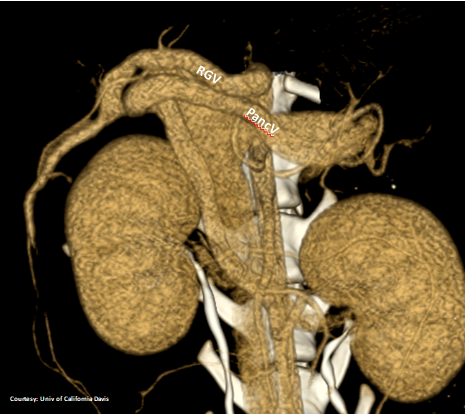

PRE-HEPATIC ENTRANCE

(Absent GSV)

“LGC +PancV -GSV” Left Gastro-Caval Shunt with Pancreatic Vein contribution and absent Gastro-splenic vein (GSV does not enter PV)

Courtesy: Nihon Univ

WEISSE 2022